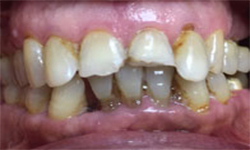

(6) Teeth Whitening

Before Treatment

After Treatment

Patient reported to us with the concern of Yellow teeth. Patient was conscious in social gatherings due to lack of confidence. Complete gum treatment and polishing was done for the patient followed by in office bleaching to achieve 2 shade whiter teeth. Home kit was a also delivered to the patient for maintenance as patient was coming from far.